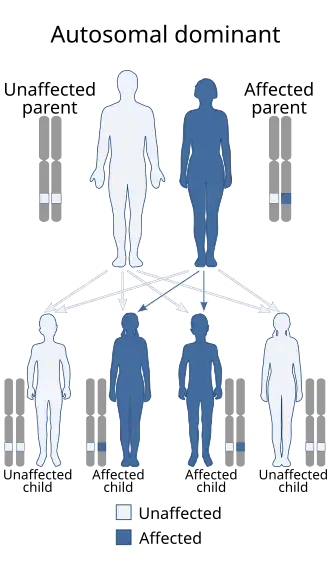

The hereditary ataxias are categorized by mode of inheritance and causative gene or chromosomal locus. The hereditary ataxias can be inherited in an autosomal dominant, autosomal recessive, or X-linked manner.

- Many types of autosomal dominant cerebellar ataxias for which specific genetic information is available are now known. Synonyms for autosomal-dominant cerebellar ataxias (ADCA) used prior to the current understanding of the molecular genetics were Marie's ataxia, inherited olivopontocerebellar atrophy, cerebello-olivary atrophy, or the more generic term "spinocerebellar degeneration." (Spinocerebellar degeneration is a rare inherited neurological disorder of the central nervous system characterized by the slow degeneration of certain areas of the brain. There are three forms of spinocerebellar degeneration: Types 1, 2, 3. Symptoms begin during adulthood.)

There are numerous types of autosomal-dominant cerebellar ataxias

There are numerous types of autosomal-dominant cerebellar ataxias -